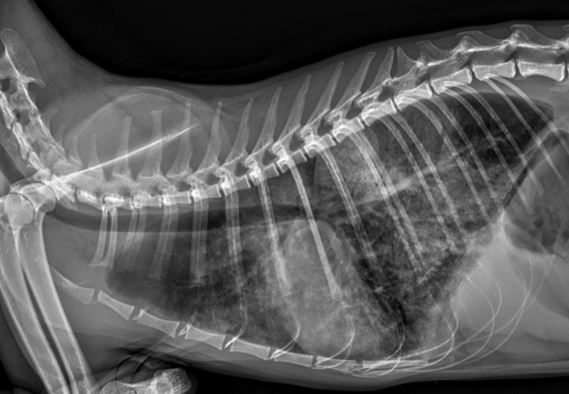

심장 질환 진단에서 가장 중요한 것은 ‘심장의 상태를 얼마나 정확하게 볼 수 있느냐’입니다. 저희 센터는 대학병원급 하이앤드 초음파 장비를 도입하여, 실시간 3D 렌더링으로 정밀 진단이 가능하며, 심장의 구조·혈류·기능을 실시간 고해상도로 관찰합니다.

미세한 판막 움직임, 혈류 속도 변화, 심방·심실 크기와 수축력까지 정밀하게 분석할 수 있어, 심장질환의 조기 발견과 치료 계획 수립에 큰 차이를 만듭니다.